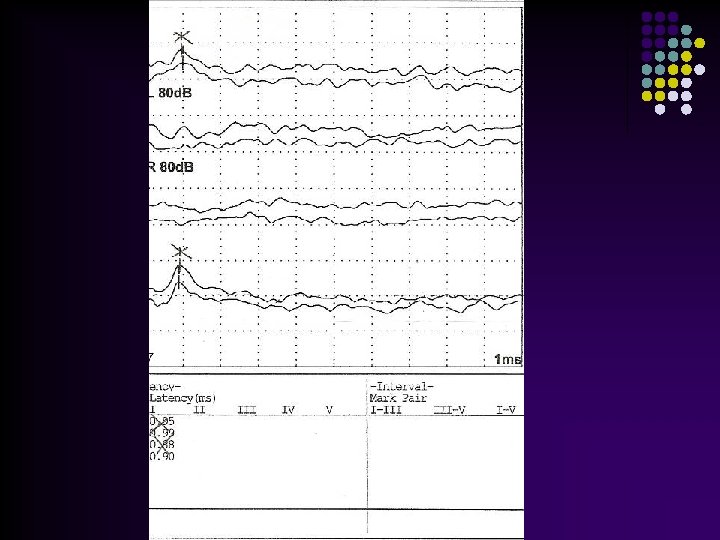

Caso Clínico Teste da Orelhinha(Triagem auditiva)= normal Estuda a capacidade da cóclea em transmitir sons para o conduto auditivo externo. l BERA (Audiometria de respostas elétricas do tronco cerebral): Analisa a ativação do VIII PAR e as estruturas auditivas do tronco cerebral. l Resultado: Provável Acusia severa; repetir em semanas l

Kernicterus, ainda um desafio Uso de Albumina: Tratamento de Choque • Hosono S, et al (Japão): 2002 58 RN ( 39, 4 sem; peso 3245 g): Bilirrubina Livre ≥ 0, 9 µg% 20 – fototerapia apenas 38 – fototerapia + albumina Potencial evocado (6 meses): Anormal: 3 (albumina) x 6 (fototerapia) www. paulomargotto. com. br Shapiro SM, 2006